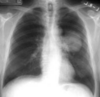

Consolidación alveolar

How well did you know this?